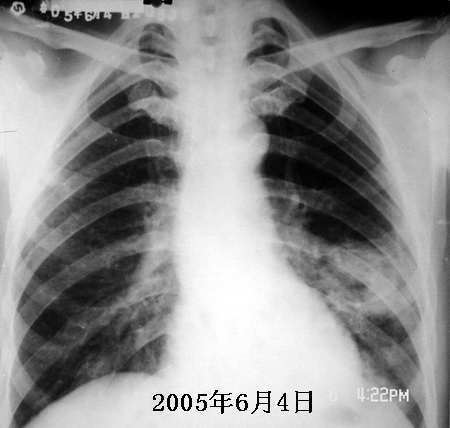

以下是引用jiajie在2005-11-6 22:07:00的发言:[br]1)左肺下叶阻塞性肺炎,胸腔积液,中心型肺癌可能大,建议纤支镜。[br]2)结合30年打石史,双肺弥漫性小结节考虑矽肺。

以下是引用sdqzwyx在2005-11-7 19:59:00的发言:[br]双肺弥漫大小不等的粟粒状结节影;肺纹理走行失去自然,粗细不均,边缘不规则,小叶间隔增厚;左上肺示不规则形致密影,从斑块边缘向周围伸出长短不一的致密索条影,临近的血管、支气管和叶间胸膜等结构受牵拉移位;左下肺示不规则团块状影,其内示空洞,洞内壁尚光整,左侧胸腔积液。右肺下叶背段亦示部分病灶融合。双肺可见局限性肺气肿。[br]诊断:结合病史符合三期矽肺表现(少数矽肺纤维斑块内可以形成空洞,一般认为是斑块中央感染引起坏死所致)但尘肺病人易合并肺结核,诊断可为三期+tb。所以此病人应进一步检查是否合并结核。